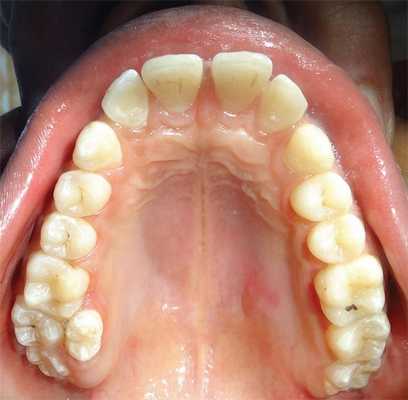

Внутриротовой осмотр выявил Класс I смыкания и отсутствие патологии расположения зубов. В дополнение к полному набору постоянных зубов обнаружен один сверхкомплектный зуб, расположенный с небной стороны между верхним первым и вторым моляром слева (Фото 1).

Фото 1: Внутриротовая фотография, показывающая парамолярное расположение сверхкомплектного зуба между верхнем первым и вторым моляром слева.

Сверхкомплектный зуб определен как парамоляр. Коронка парамоляра имела два бугорка и весьма сильно напоминала строение постоянного премоляра. Зуб повернут по оси, с расположением щечной поверхности дистально и мезиальной поверхности щечно. На мезиальной стороне парамоляра обнаружено кариозное поражение (Фото 2). Осмотр мягких тканей выявил воспаление пародонта между первым и вторым молярами и парамоляром. Сделаны рентгеновские снимки: панорамный, прицельный и окклюзионный. Чтение панорамного снимка было затруднено из-за небного расположения зуба. На прицельном и окклюзионных снимках обнаружено, что сверхкомплектный зуб поражен кариесом и имеет один корень (Фото 3 и 4).